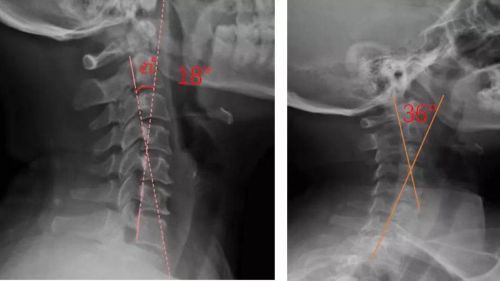

患者適配前后側位X光,佩戴前18°,適配后36°

對于頸椎病患者,合理設計的頸椎枕,能夠緊密適合頸椎,矯正頸椎生理曲度;再根據頸椎曲度改善情況,隨時間慢慢調整3D打印頸椎枕曲度,使變直的頸椎逐漸形成正常的生理曲度,改善頸肩痛的癥狀。

我們通過對頸部進行光學掃描與頸椎側位X光檢查,測量頸椎曲度,由專業矯形器師結合患者的情況設計個性化頸椎枕,部分或全部3D打印工藝制作完成,矯正頸椎的生理曲度?;颊哌m配后拍攝X光片,做到精準矯正與治療,避免使用不適和矯枉過正。